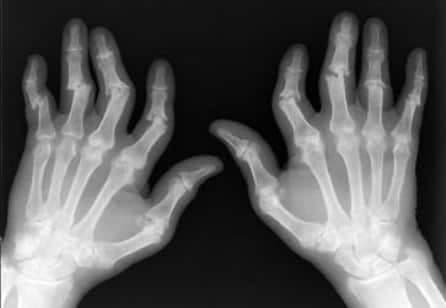

Dikkatli bir hikaye ve fizik muayene ile değerlendirme tanı için en önemli unsurdur. Klinik bulgular eşliğinde röntgen filmleri tanıya yardımcı olur.